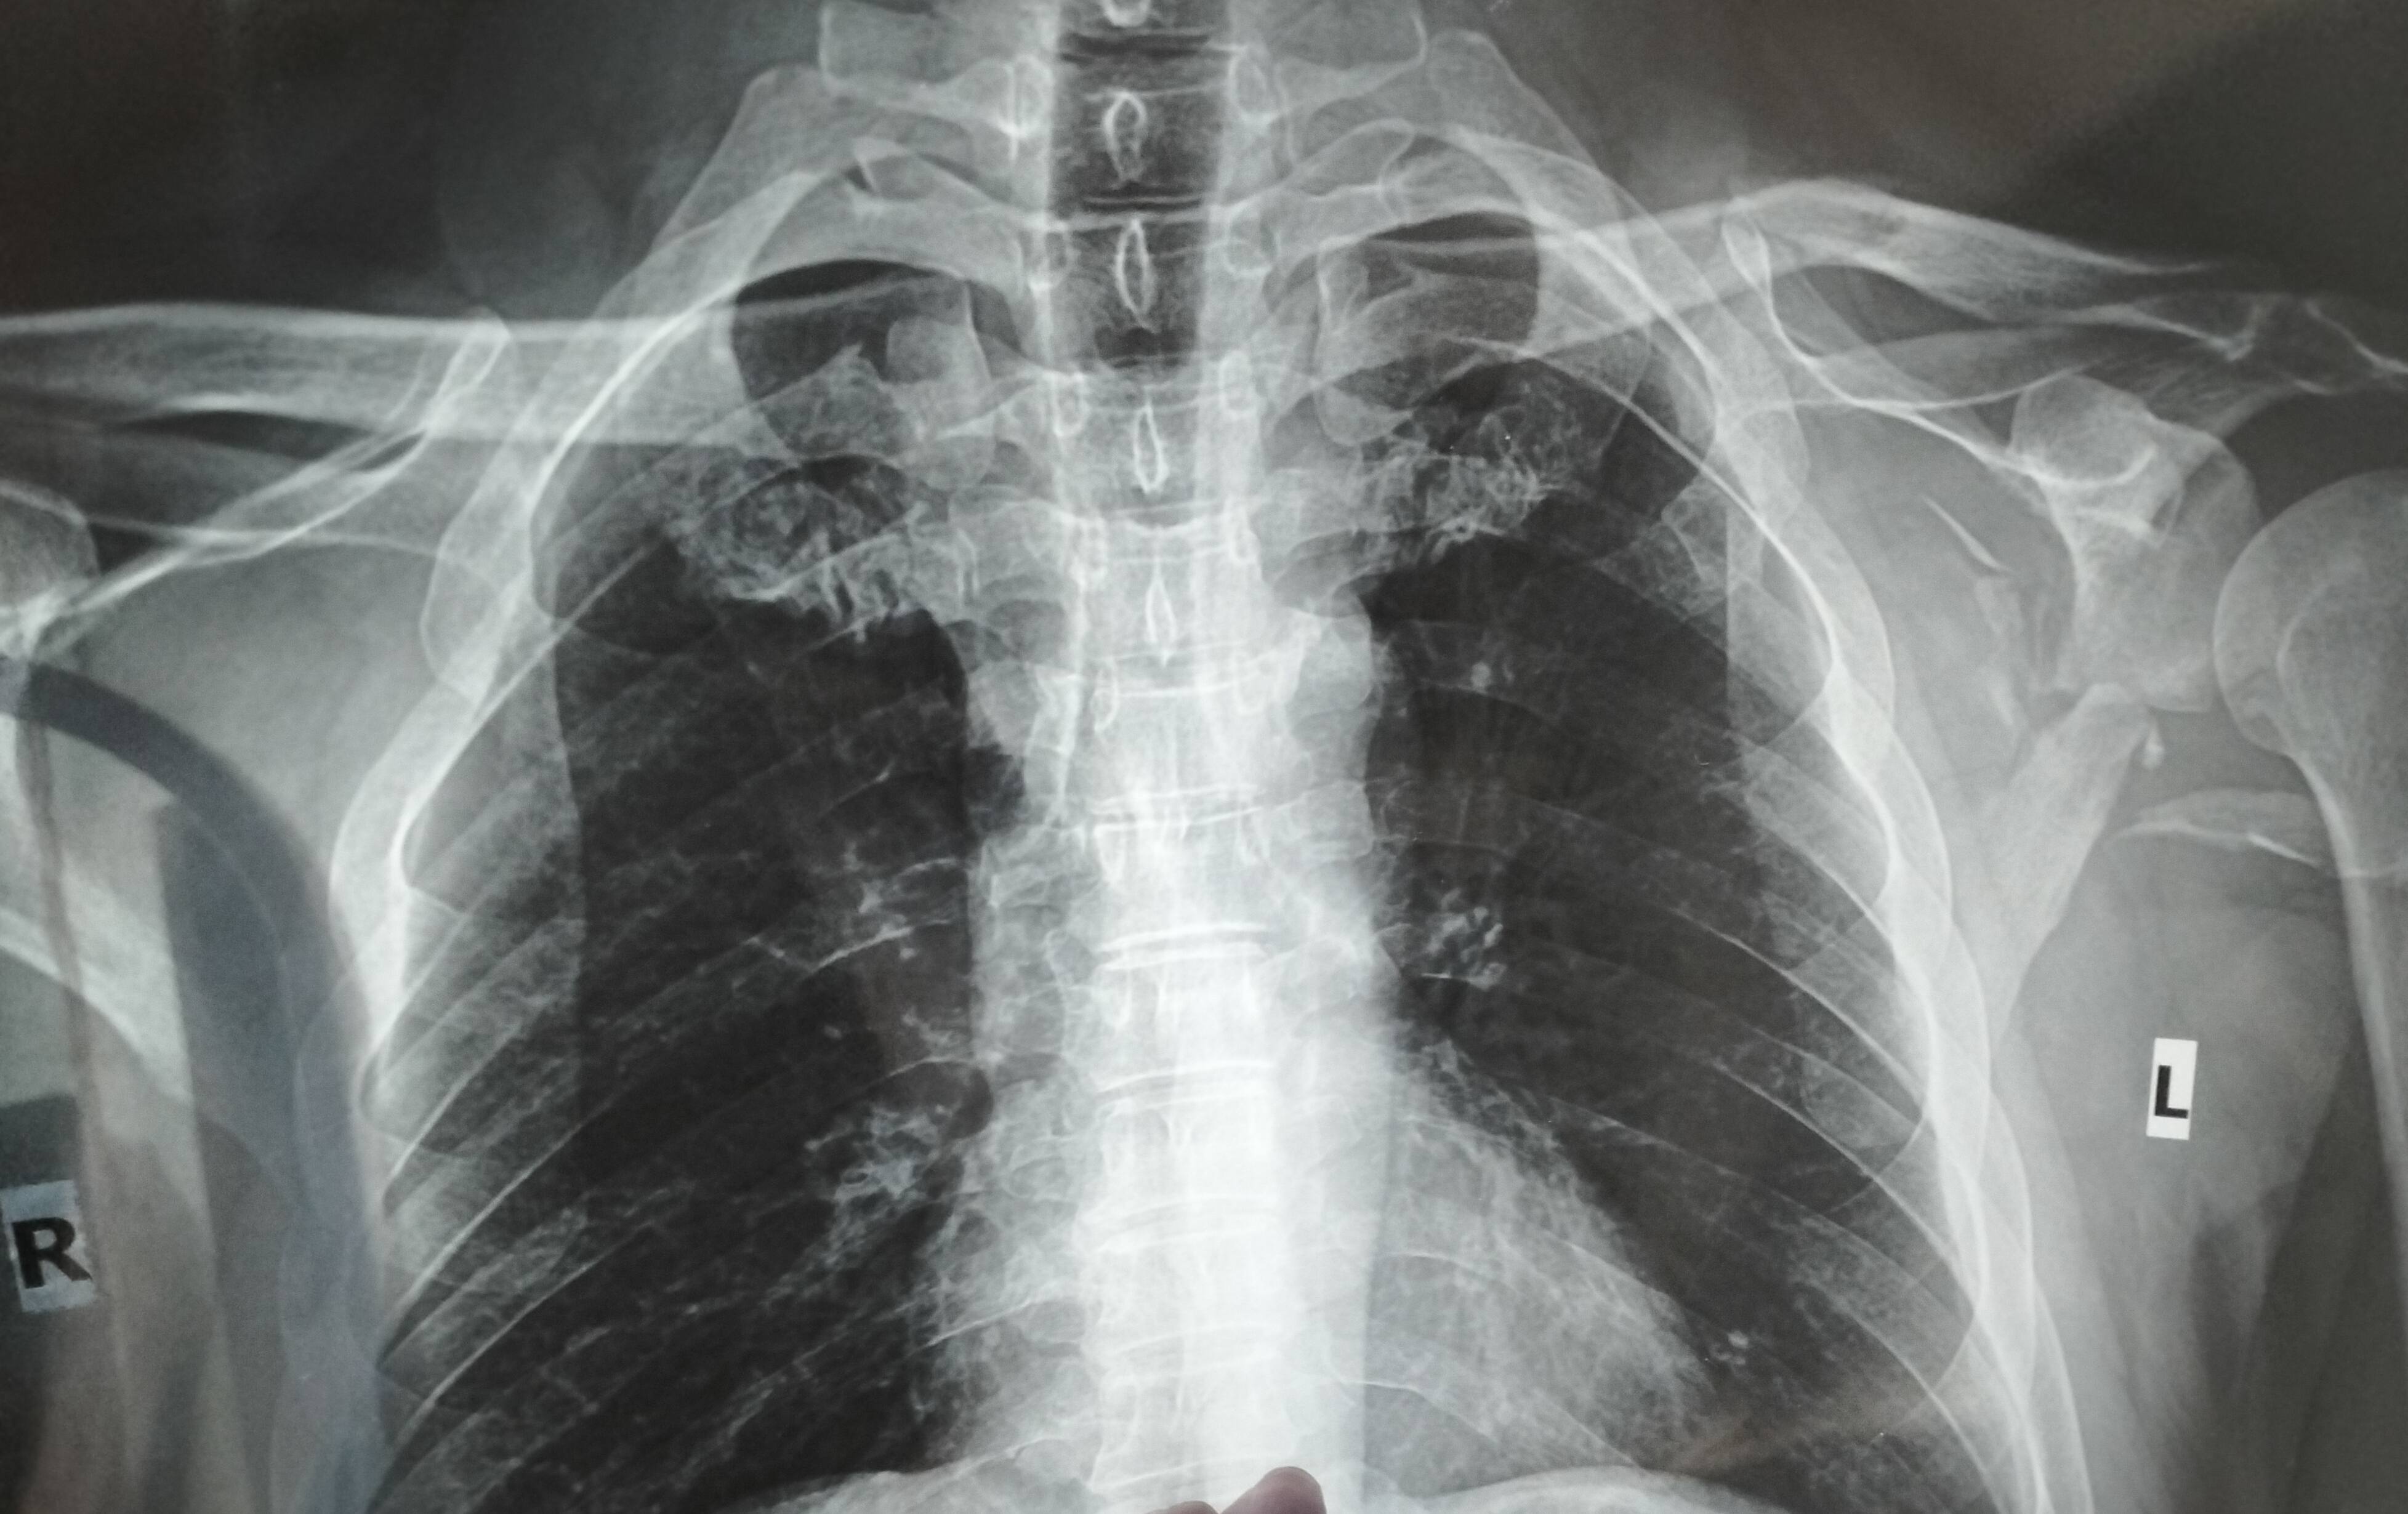

On 22th October, 2022 my clavicle and scabula got fractured due to a bike accident. Is it okay if it gets joined automatically? Or is there any better way to treat it so that no problem occurs in future?

Some doctors suggested that an operation can be conducted to straighten the clavicle, some said operation isn't needed. What's your suggestion?

By the way, I've sent messages and x-ray images in your WhatsApp. Your suggestion would be much appreciated.